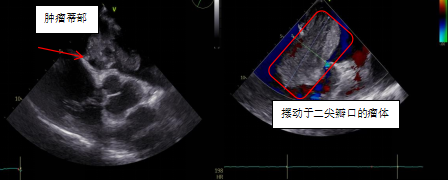

患者鄭大爺,因“反復(fù)勞累性心累、氣促2+月,加重10+天”到我院胸心血管外科就診。本次病情發(fā)作后,鄭大爺夜間無法平臥,呈端坐呼吸,伴咳嗽、咳痰,為白色泡沫痰,心悸、心慌明顯,并感頭暈,測(cè)血壓偏低,為休克狀態(tài)(80-90/40-50mmHg)。入院經(jīng)心臟彩超、胸部影像學(xué)等相關(guān)檢查,發(fā)現(xiàn)導(dǎo)致鄭大爺癥狀的元兇:“巨大左心房占位”,支持粘液瘤樣改變,同期發(fā)現(xiàn)患者伴有卵圓孔未閉、三尖瓣中度關(guān)閉不全等心臟問題。

患者心臟彩超結(jié)果